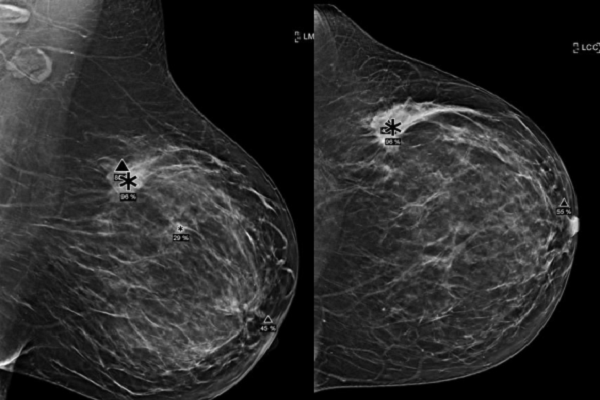

Trong hành lang các khoa chẩn đoán hình ảnh, nơi những tấm nhũ ảnh được phóng to, thu nhỏ hàng trăm lần mỗi ngày, một thay đổi sâu sắc đang diễn ra. Trí tuệ nhân tạo (AI) - trước đây chỉ là khái niệm xuất hiện trong hội thảo hoặc phòng nghiên cứu - giờ đã lặng lẽ bước vào thực tế lâm sàng. Nó ngồi cạnh bác sĩ, soi từng milimet hình ảnh, đánh dấu những điểm bất thường mà mắt thường có thể bỏ qua.

Điều này không phải lời khen mang tính quảng cáo. Khi những thuật toán học sâu có thể phân tích hàng triệu pixel trực tiếp từ ảnh, AI không chỉ mô phỏng cách con người đánh giá hình ảnh mà thực sự trở thành “con mắt thứ hai” - sắc bén và kiên định hơn.

Phân tích của bác sĩ Nguyễn Tín Trung cho thấy Deep Learning (học sâu) mở ra cánh cửa mới. Thay vì trông đợi vào vài chục đặc điểm mô tả, máy học sâu tự xử lý hàng nghìn pixel thô, nhiều lớp dữ liệu phức tạp, giống như bộ não con người đang được huấn luyện mỗi ngày. Từ đó, hệ thống như Genius AI Detection không chỉ “nhìn” hình ảnh mà còn “hiểu” cấu trúc tổn thương.

Sự khác biệt rõ nhất nằm ở độ chính xác. Khi kết hợp với tầm soát ung thư vú sớm bằng Tomosynthesis (DBT) - nhũ ảnh 3D giúp tách riêng từng lớp mô - AI không còn bị đánh lừa bởi sự chồng lấp mô vú như ảnh 2D truyền thống. Nhờ đó, độ nhạy trong phát hiện ung thư tăng đáng kể, độ đặc hiệu cũng tăng lên, giúp giảm đáng kể các trường hợp dương tính giả.